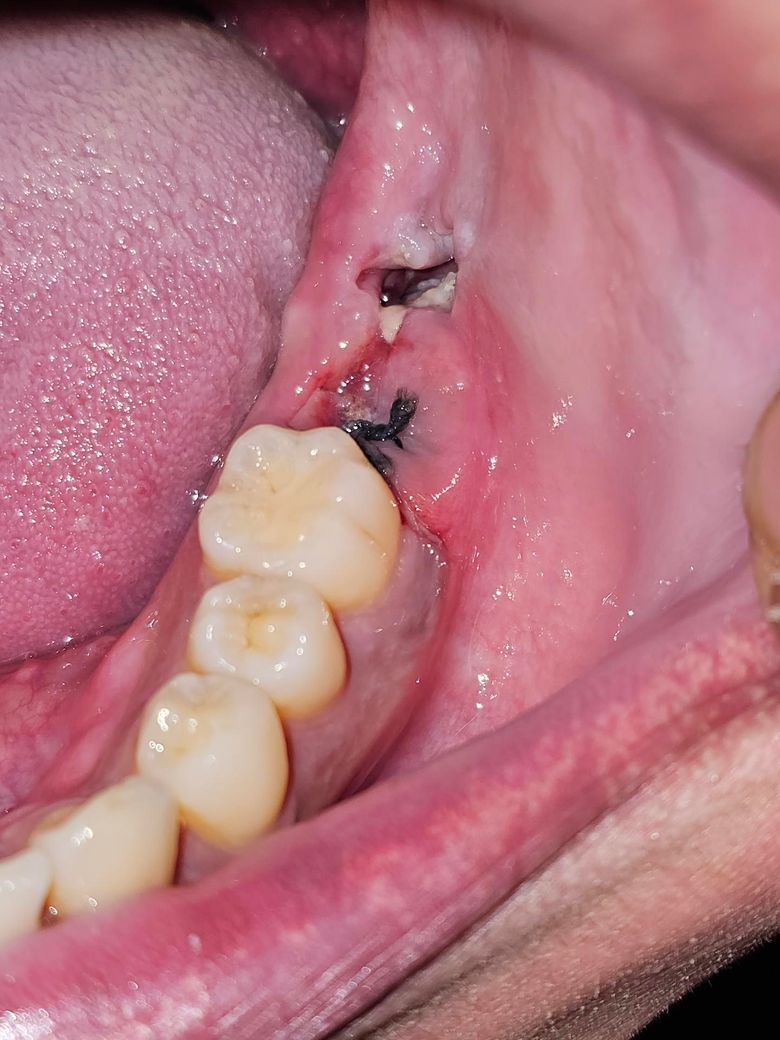

발치 한 곳 잘 아물고 있는지 궁금해서 남겨 봅니다.

목요일에 발치하여 현지 74시간 가량 지났습니다.

평소에는 통증이 없는데 아직은 입 벌릴때 약간 불편감이 있고 한번씩 땡끼는 느낌 나는거 말곤 크게 아프거나 하진 않습니다.

드라이소켓 걱정은 안해도 되는거죠?

사진으로 봤을 경우 문제가 없이 잘 아물고 있는 것으로 보입니다. 너무 걱정하지 않아도 됩니다.

1. 드라이소켓은 원래 발치 후 3~5일차에 잘 생깁니다. 아직 안심할 단계는 아니고요. 발치 후 주의사항 계속 잘 지켜주셔야 합니다.

2. 잇몸 아직 치유가 덜 진행되었습니다